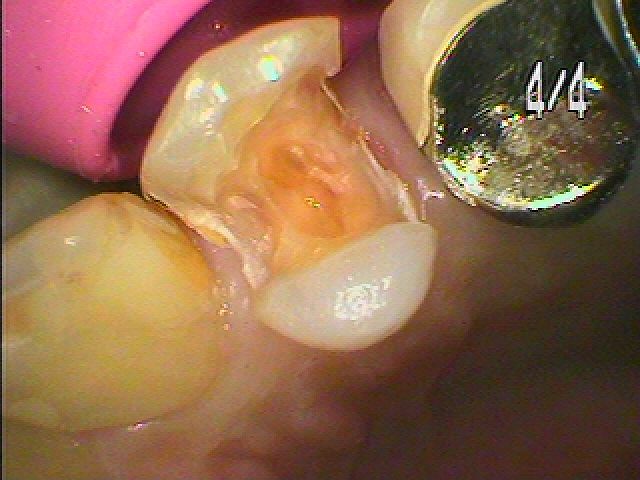

虫歯を除去していきました